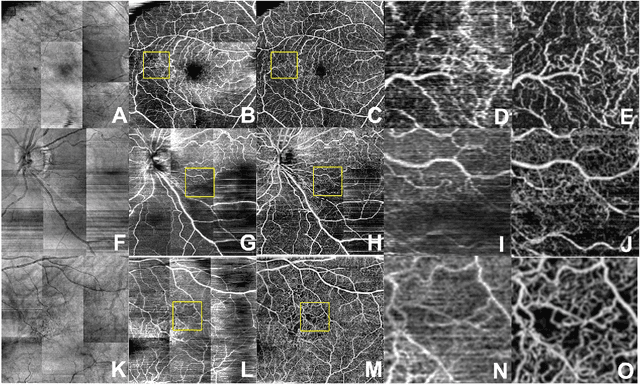

Abstract:Despite significant advances in artificial intelligence (AI) for computer vision, its application in medical imaging has been limited by the burden and limits of expert-generated labels. We used images from optical coherence tomography angiography (OCTA), a relatively new imaging modality that measures perfusion of the retinal vasculature, to train an AI algorithm to generate vasculature maps from standard structural optical coherence tomography (OCT) images of the same retinae, both exceeding the ability and bypassing the need for expert labeling. Deep learning was able to infer perfusion of microvasculature from structural OCT images with similar fidelity to OCTA and significantly better than expert clinicians (P < 0.00001). OCTA suffers from need of specialized hardware, laborious acquisition protocols, and motion artifacts; whereas our model works directly from standard OCT which are ubiquitous and quick to obtain, and allows unlocking of large volumes of previously collected standard OCT data both in existing clinical trials and clinical practice. This finding demonstrates a novel application of AI to medical imaging, whereby subtle regularities between different modalities are used to image the same body part and AI is used to generate detailed and accurate inferences of tissue function from structure imaging.